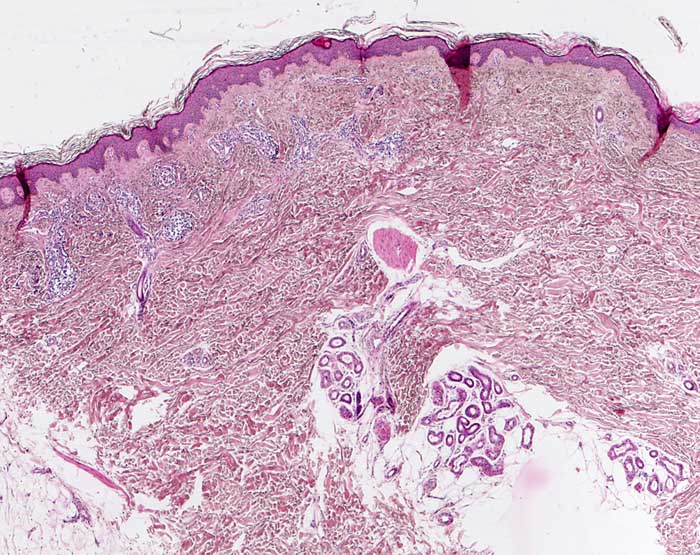

Die klassischen histologischen Befunde finden sich am deutlichsten in frühen schuppenden Papeln sowie nahe am Rand wachsender erythematosquamöser Plaques. Die behandelte Psoriasis ist histologisch hingegen schwer von anderen Dermatosen abgrenzbar.

Morphologische Merkmale:

• Hyperparakeratotische Verhornung der Epidermis (verdickte, kernhaltige Hornschicht)

• Ausgedünntes oder fehlendes Stratum granulosum

• Psoriasiforme Epithelhyperplasie: Gleichmässige Akanthose mit verlängerten epidermalen Reteleisten, die zur Basis verbreitert sind und hochgezogene dermale Papillen.

• Munro-Mikroabszesse (Ansammlung neutrophiler Granulozyten in der Hornschicht und subkorneal)

• Verschmälerung der suprapapillären Epidermis

• Dilatierte gewundene Kapillaren im Bereich der papillären Dermis

• Papillenödem

• Oberflächlich perivaskuläres lymphozytäres Entzündungsinfiltrat